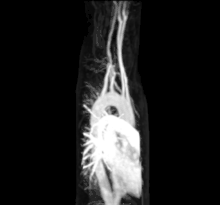

![]() Кровообіг людини. На малюнку зображені артерії, капіляри та вени, якими проходить кров | |